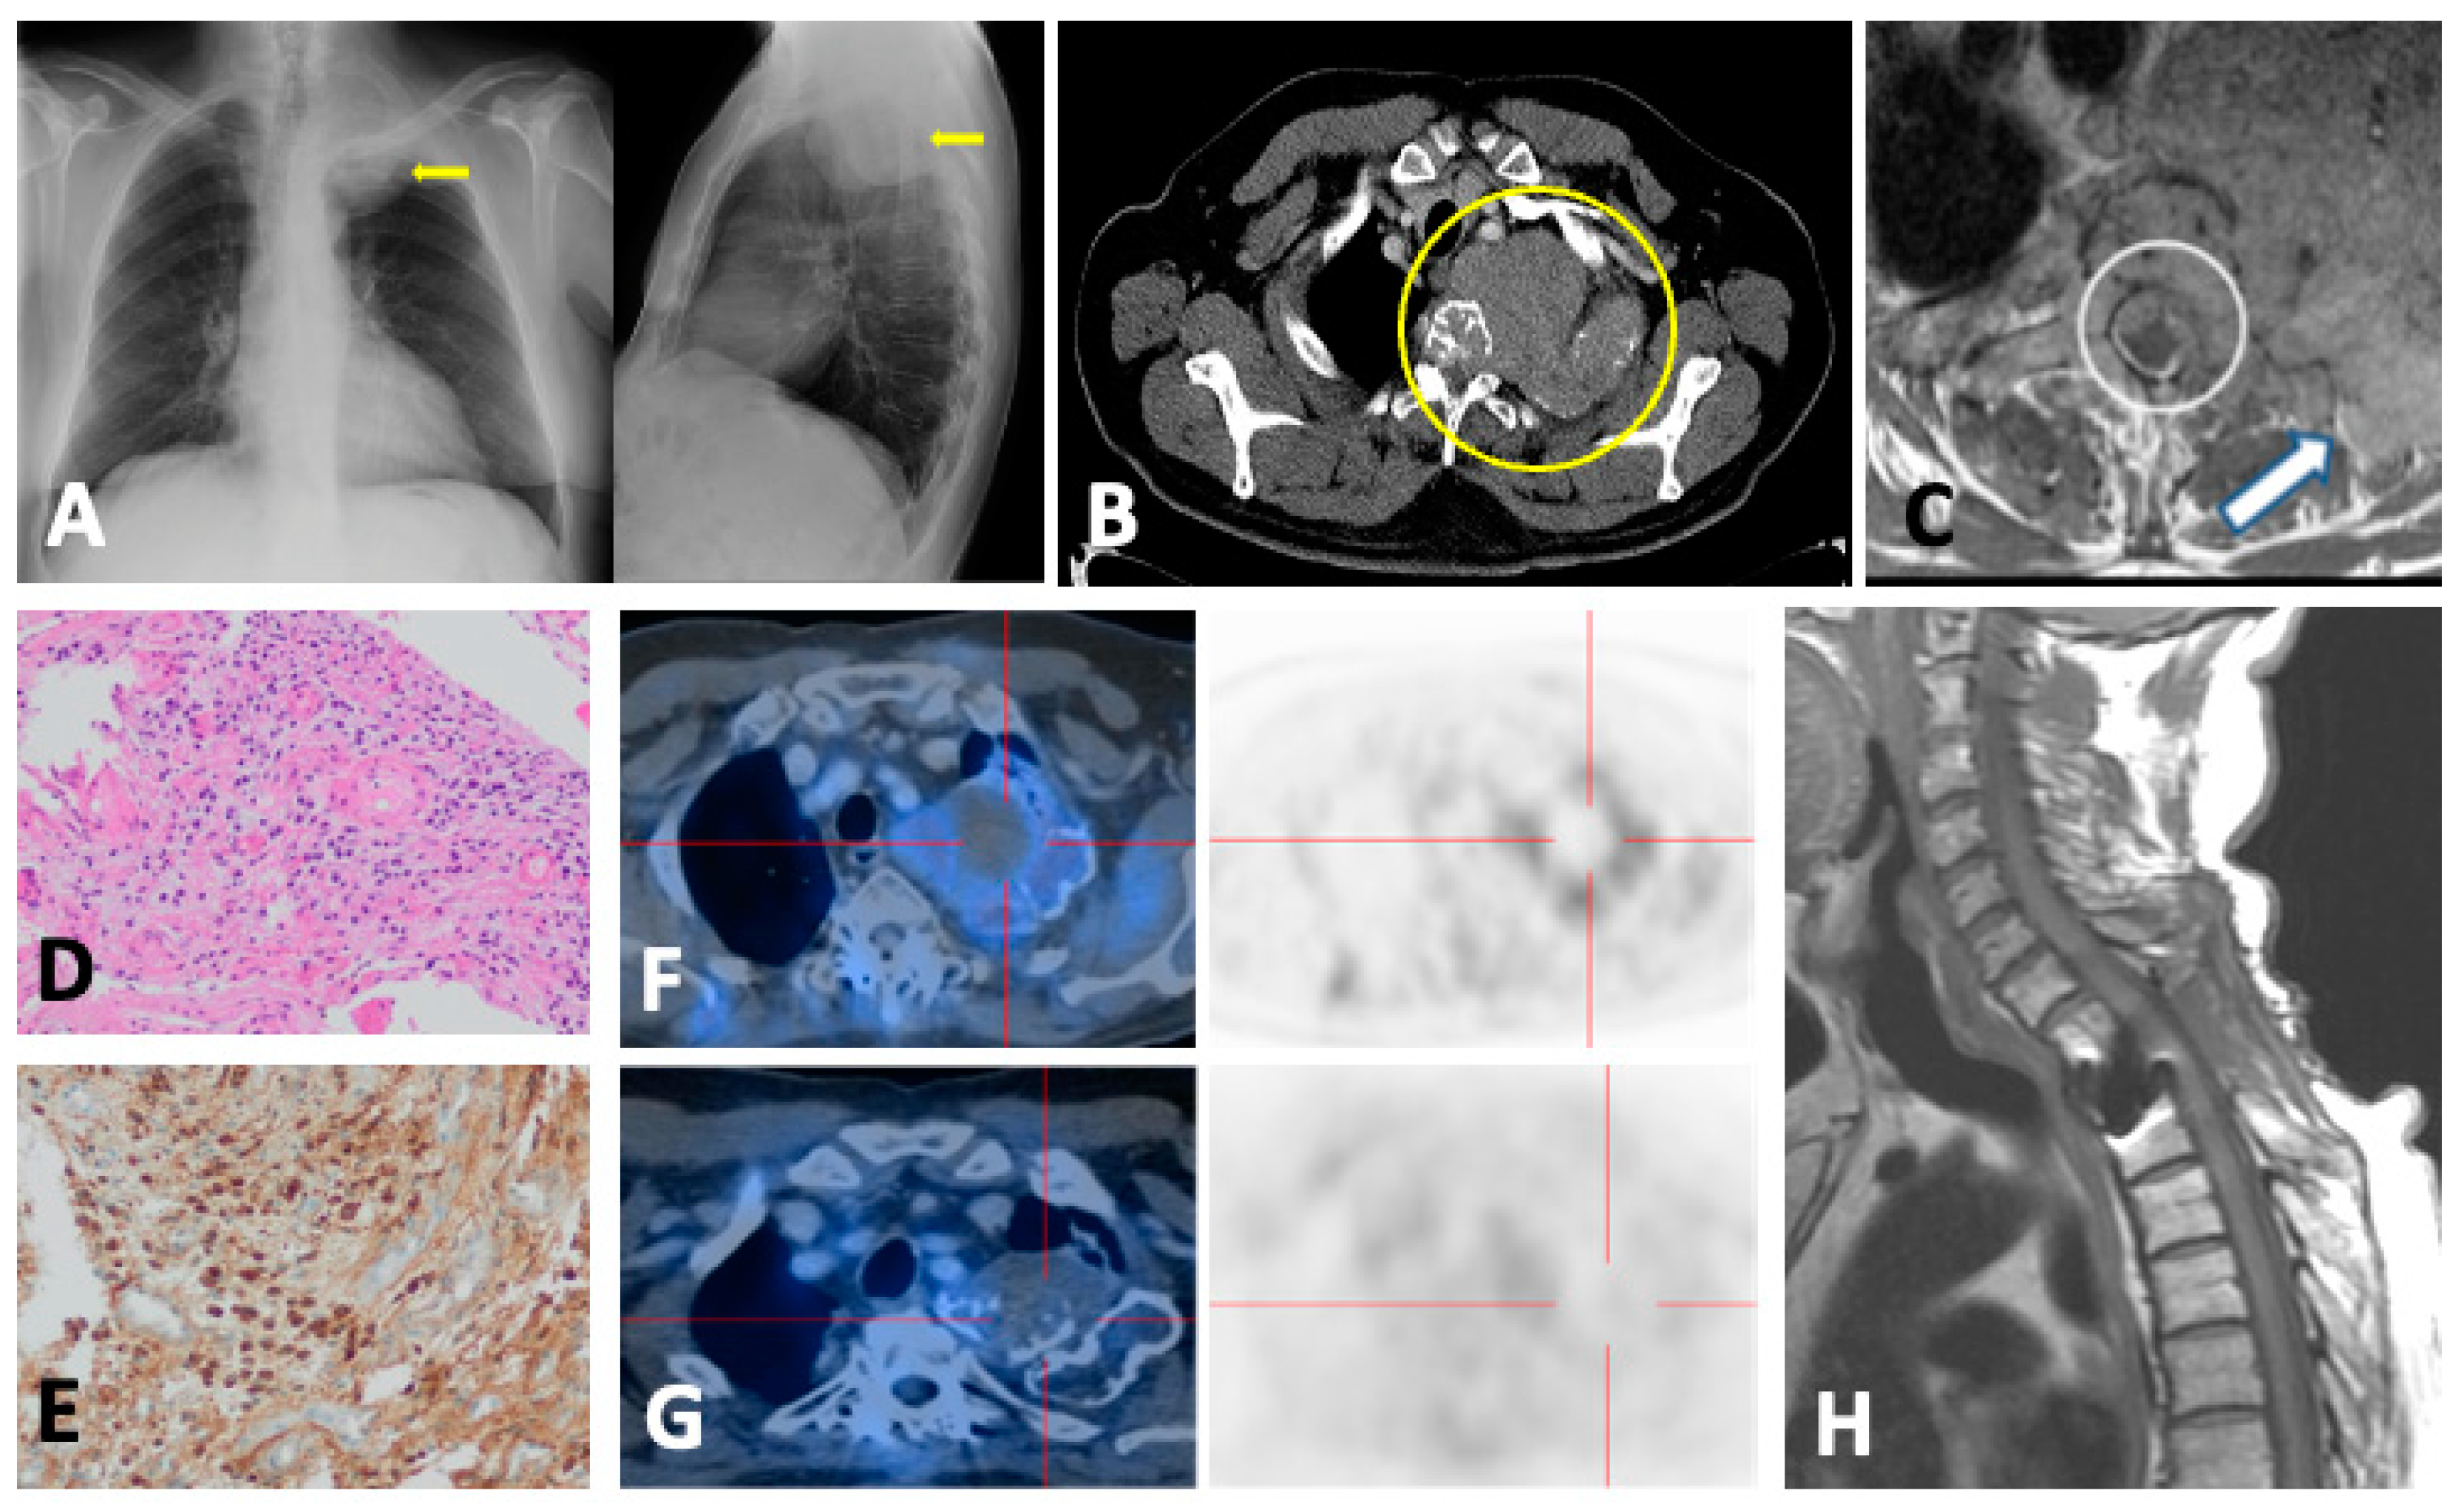

5.1. PET/CT

5.1.1. Technique and Image Analysis

5.1.2. Response Measurement

5.1.3. Minimal Residual Disease

5.1.4. Alternative PET Tracers

5.1.5. FDG-PET/CT vs. WBMRI

5.2. FDG-PET/MRI

6. Plasmacytoma and Extramedullary MM